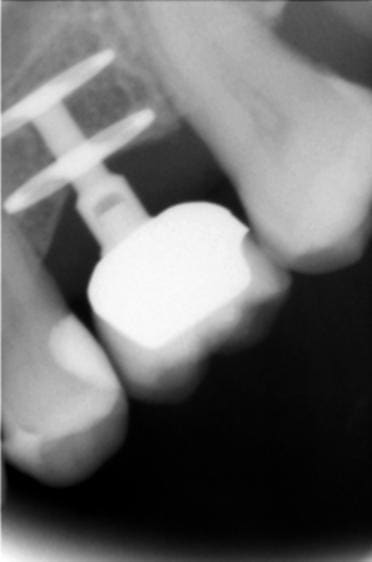

C'était un master L 3.3

3.3 étant le diamètre du fût, et 4mm le diamètre du col.

Je n'en ai posé que très peu juste pour essai, j'ai laissé tomber depuis

Quant à la déclaration de matériovigilance , ça me paraît une bonne idée, je vais m'en occuper.

J'ai transmis le N° de lot au fabricant, j'attends